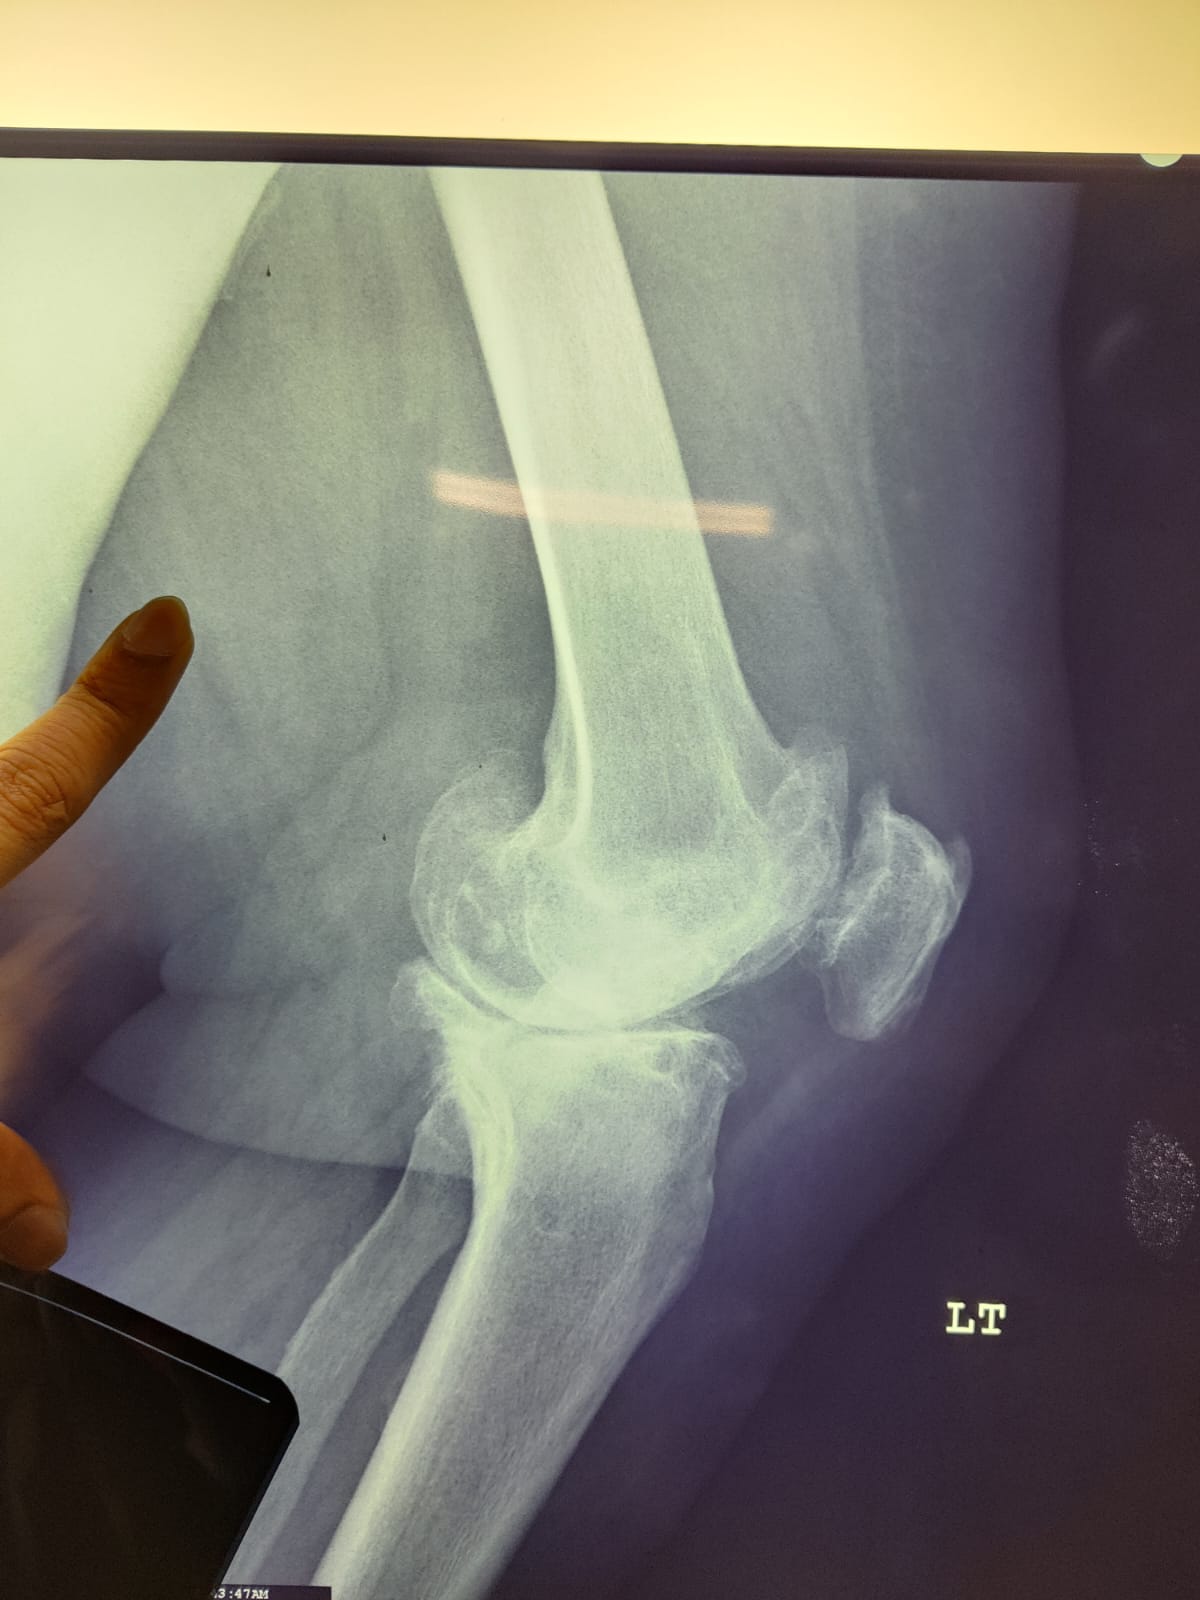

62 year old female with stage 4 OA

Primary Left TKR

Pre-op images of Right Knee